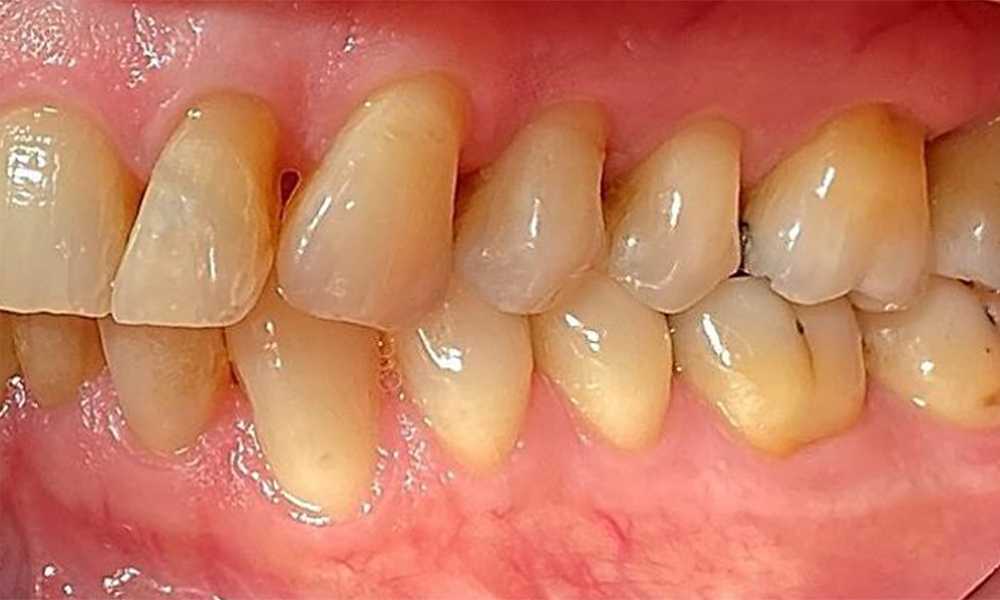

Right lateral view. Loss of the interdental papillae.

Fig. 3 Right lateral view. Loss of the interdental papillae. © Dr R. Krapf

Left lateral view including the recessions.

Fig. 4 Left lateral view including the recessions. © Dr R. Krapf

The patient has stage II, grade B periodontitis (5). At 1 to 3 mm, the clinical probing depths were within the physiological range. Localized probing depths of 5 mm were observed on the mesiopalatal aspects on both 17 and 27. There are generalized recessions of 1–3 mm with partial loss of the interdental papillae (Fig. 2, Fig. 3, Fig. 4)